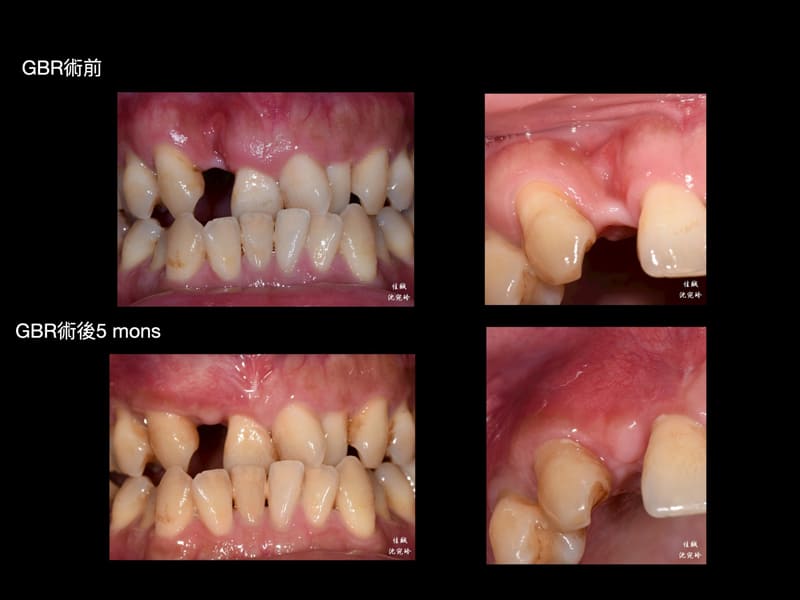

案例分享 首頁 案例分享 『植牙困難』案例分享 MORE 案例分享『矯正前之困難補骨』 MORE 案例分享『困難植牙』 MORE 案例分享『牙齒凌亂,不敢開懷大笑該怎麼辦?』 MORE 案例分享『斷裂器械移除』 MORE 案例分享『全口重建』 MORE 案例分享『活性牙髓治療(覆髓)- 蛀牙免根管治療的新選擇!』 MORE 案例分享『牙齒斷裂,利用水雷射補骨重建』 MORE 案例分享『上顎後牙區角質化上皮移植術(FGG)』 MORE 案例分享『第三代LITETOUCH水雷射舌繫帶切除』 MORE «1»